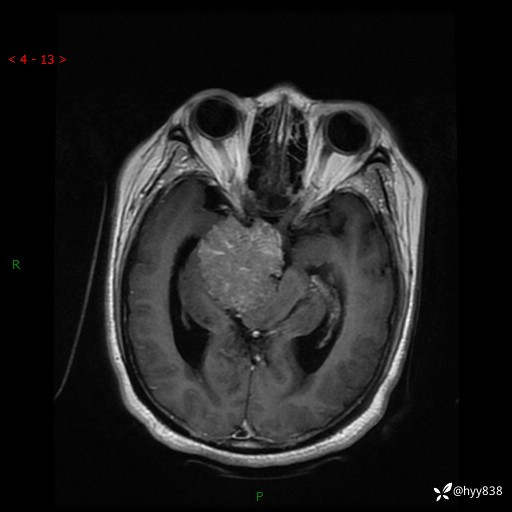

颅脑MRI平扫+增强